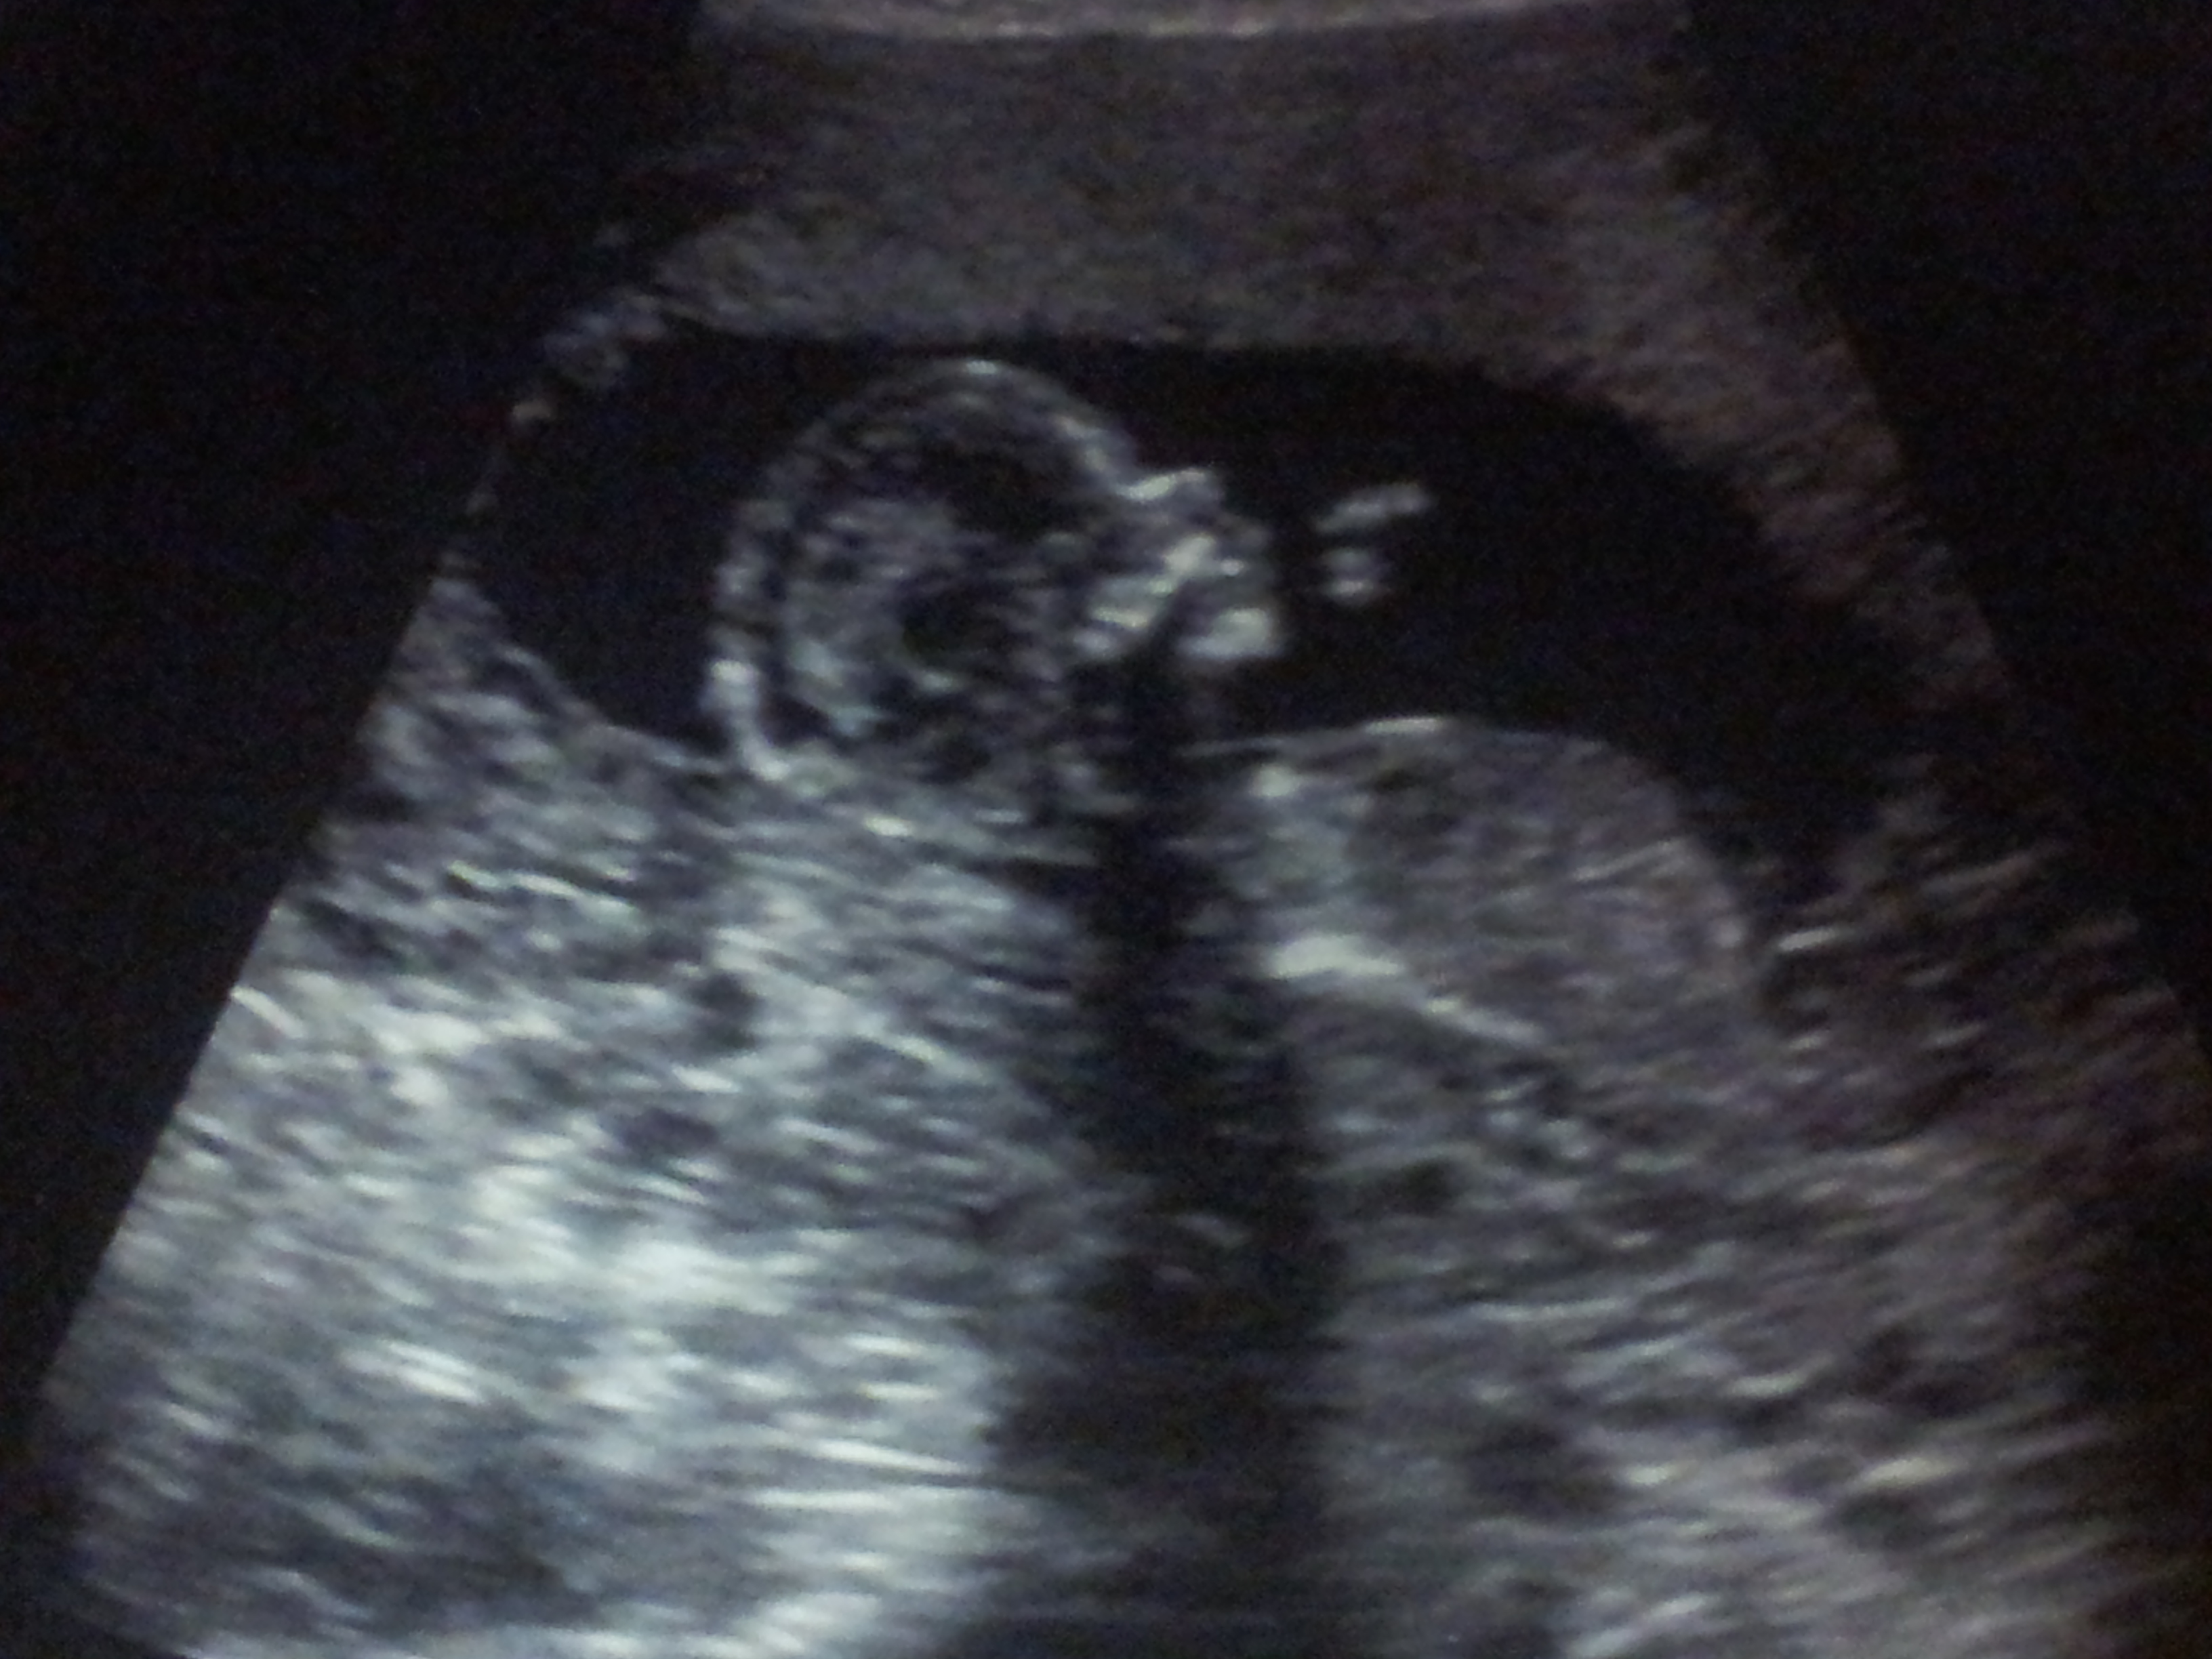

Had our NT scan this week! PIP

We had our NT scan Monday and everything looked fantastic!! We're waiting on the panorama blood test results but the doctor had no concerns based off of the u/s. Here's a pic of our little one